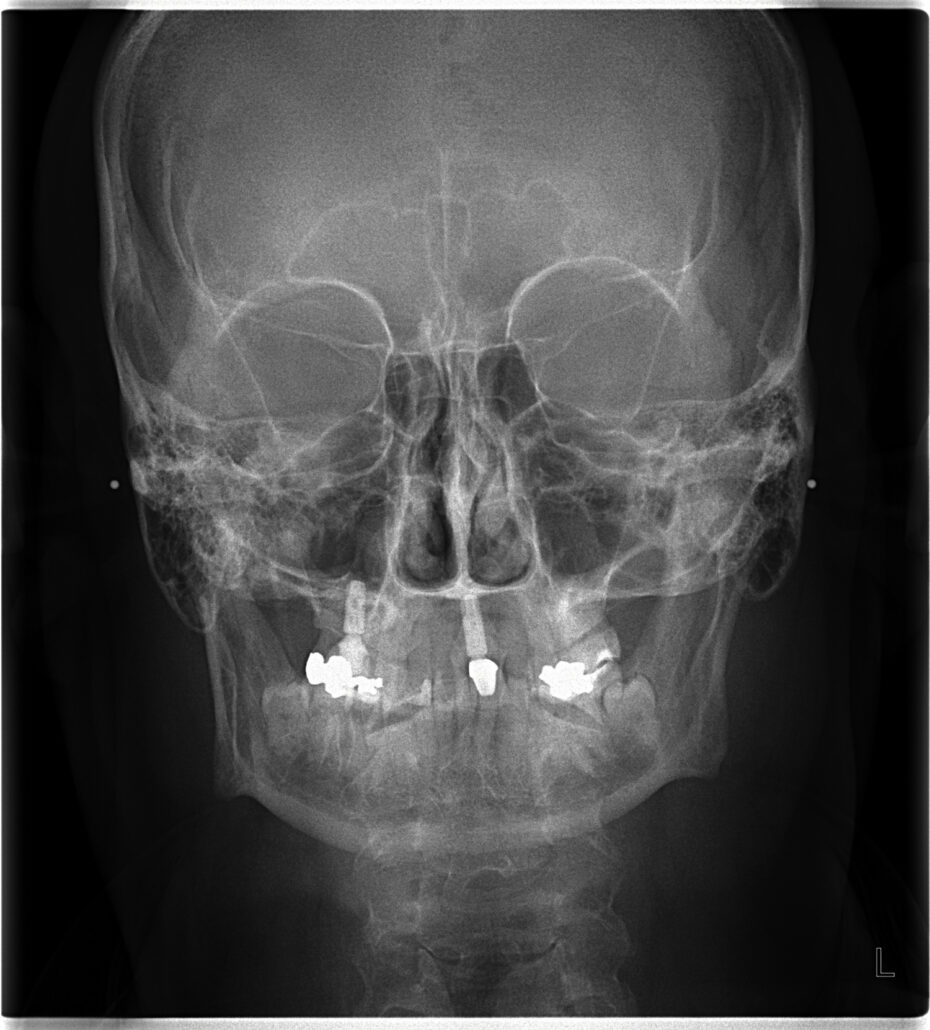

CEPH X-Ray

A cephalometric x-ray is a unique tool, which enables the dentist to capture a complete radiographic image of the side of the face. X-rays, in general, offer the dentist a way to view the teeth, jawbone and soft tissues beyond what can be seen with the naked eye. Cephalometric X-rays are extraoral, meaning that no plates or film are inserted into the mouth. Cephalometric and panoramic X-rays display the nasal and sinus passages, which are missed by intraoral bitewing X-rays.

Cephalometric X-rays are not as common as “full sets” or bitewing X-rays, but they serve several important functions:

- Provide information about “bad bites” or malocclusions.

- Identify fractures and other injuries to the teeth and jawbone.

After capturing cephalometric X-rays, the dentist will be able to see a complete side profile of the head. This can assist in orthodontic planning, and allow an immediate evaluation of how braces might impact the facial profile and teeth. Another common use for this type of X-ray is to determine specific measurements prior to the creation and placement of dental implants.